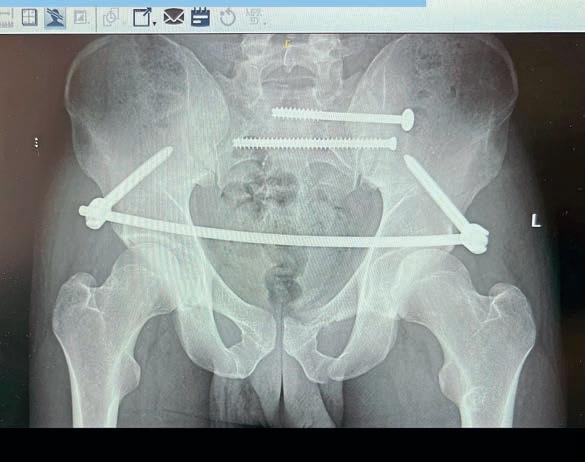

Isaid in my last column that I was hoping to be writing about a successful race week again soon, but that’s going to have to wait until next month now, I’m afraid. I fully understood the complexity of my pelvis injury at the time of my accident, but as every other racer out there will tell you, we always think we’ll be back sooner than the doctor says. In fact, I still am hoping to be back up and running a week or two ahead, but being ready to race at Brands Hatch was always going to be a little too ambitious... I had a go at thinking I’d be ready anyway. Oh well, that boat has sailed, and as gutting as it will be to see my competitors pull another big points haul over me, the most important thing is to make my comeback when I’m 100% fit and healthy and then really take it to them at Thruxton. That’s the plan, anyway. I must have had at least 20 hyperbaric sessions since I got home, but it’s a job to know how much that has improved the healing process. It’s the unknown, and everyone is asking if I’ve felt any difference from doing it. The honest answer is probably not, but my doctor was impressed with my progress at my last check-up, so who knows.

I finally have the date for the removal of my pelvic fixation bar, and the doctor wants to keep the woodscrews in for the foreseeable as they shouldn’t cause any bother… I’m just hoping I don’t stumble across a big magnet anytime soon.